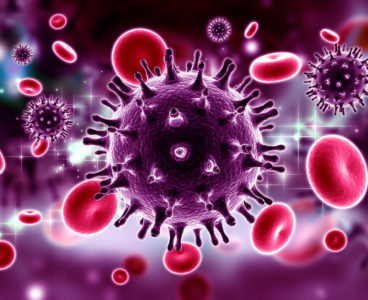

Scientists Find Missing Clue to How HIV Hacks Cells to Propagate Itself